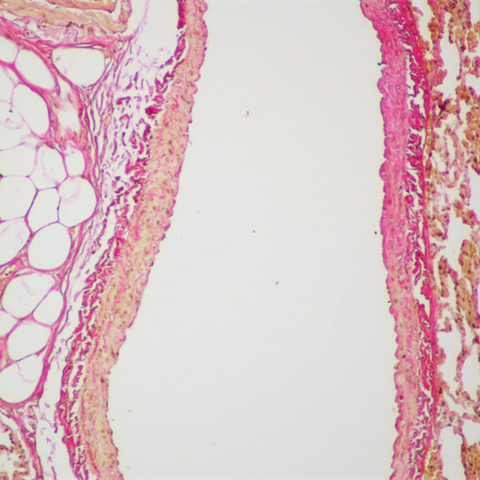

VG染色样片参考:

胶原纤维:鲜红色 肌纤维: 黄*色 红细胞: 黄*色 细胞核: 蓝黑或灰色。